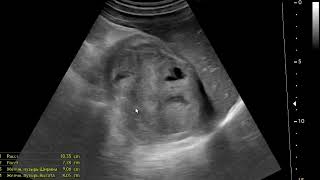

Многие симптомы и результаты дополнительных исследований могут указывать на вероятность наличия опухоли. Например, наличие опухоли на рентгенограммах, компьютерной томографии (КТ) или магнитно-резонансной томографии (МРТ) может подтвердить наличие рака. К тому же, повышенные уровни определенных маркеров рака в крови или других биологических жидкостях могут также указывать на возможность развития опухоли.